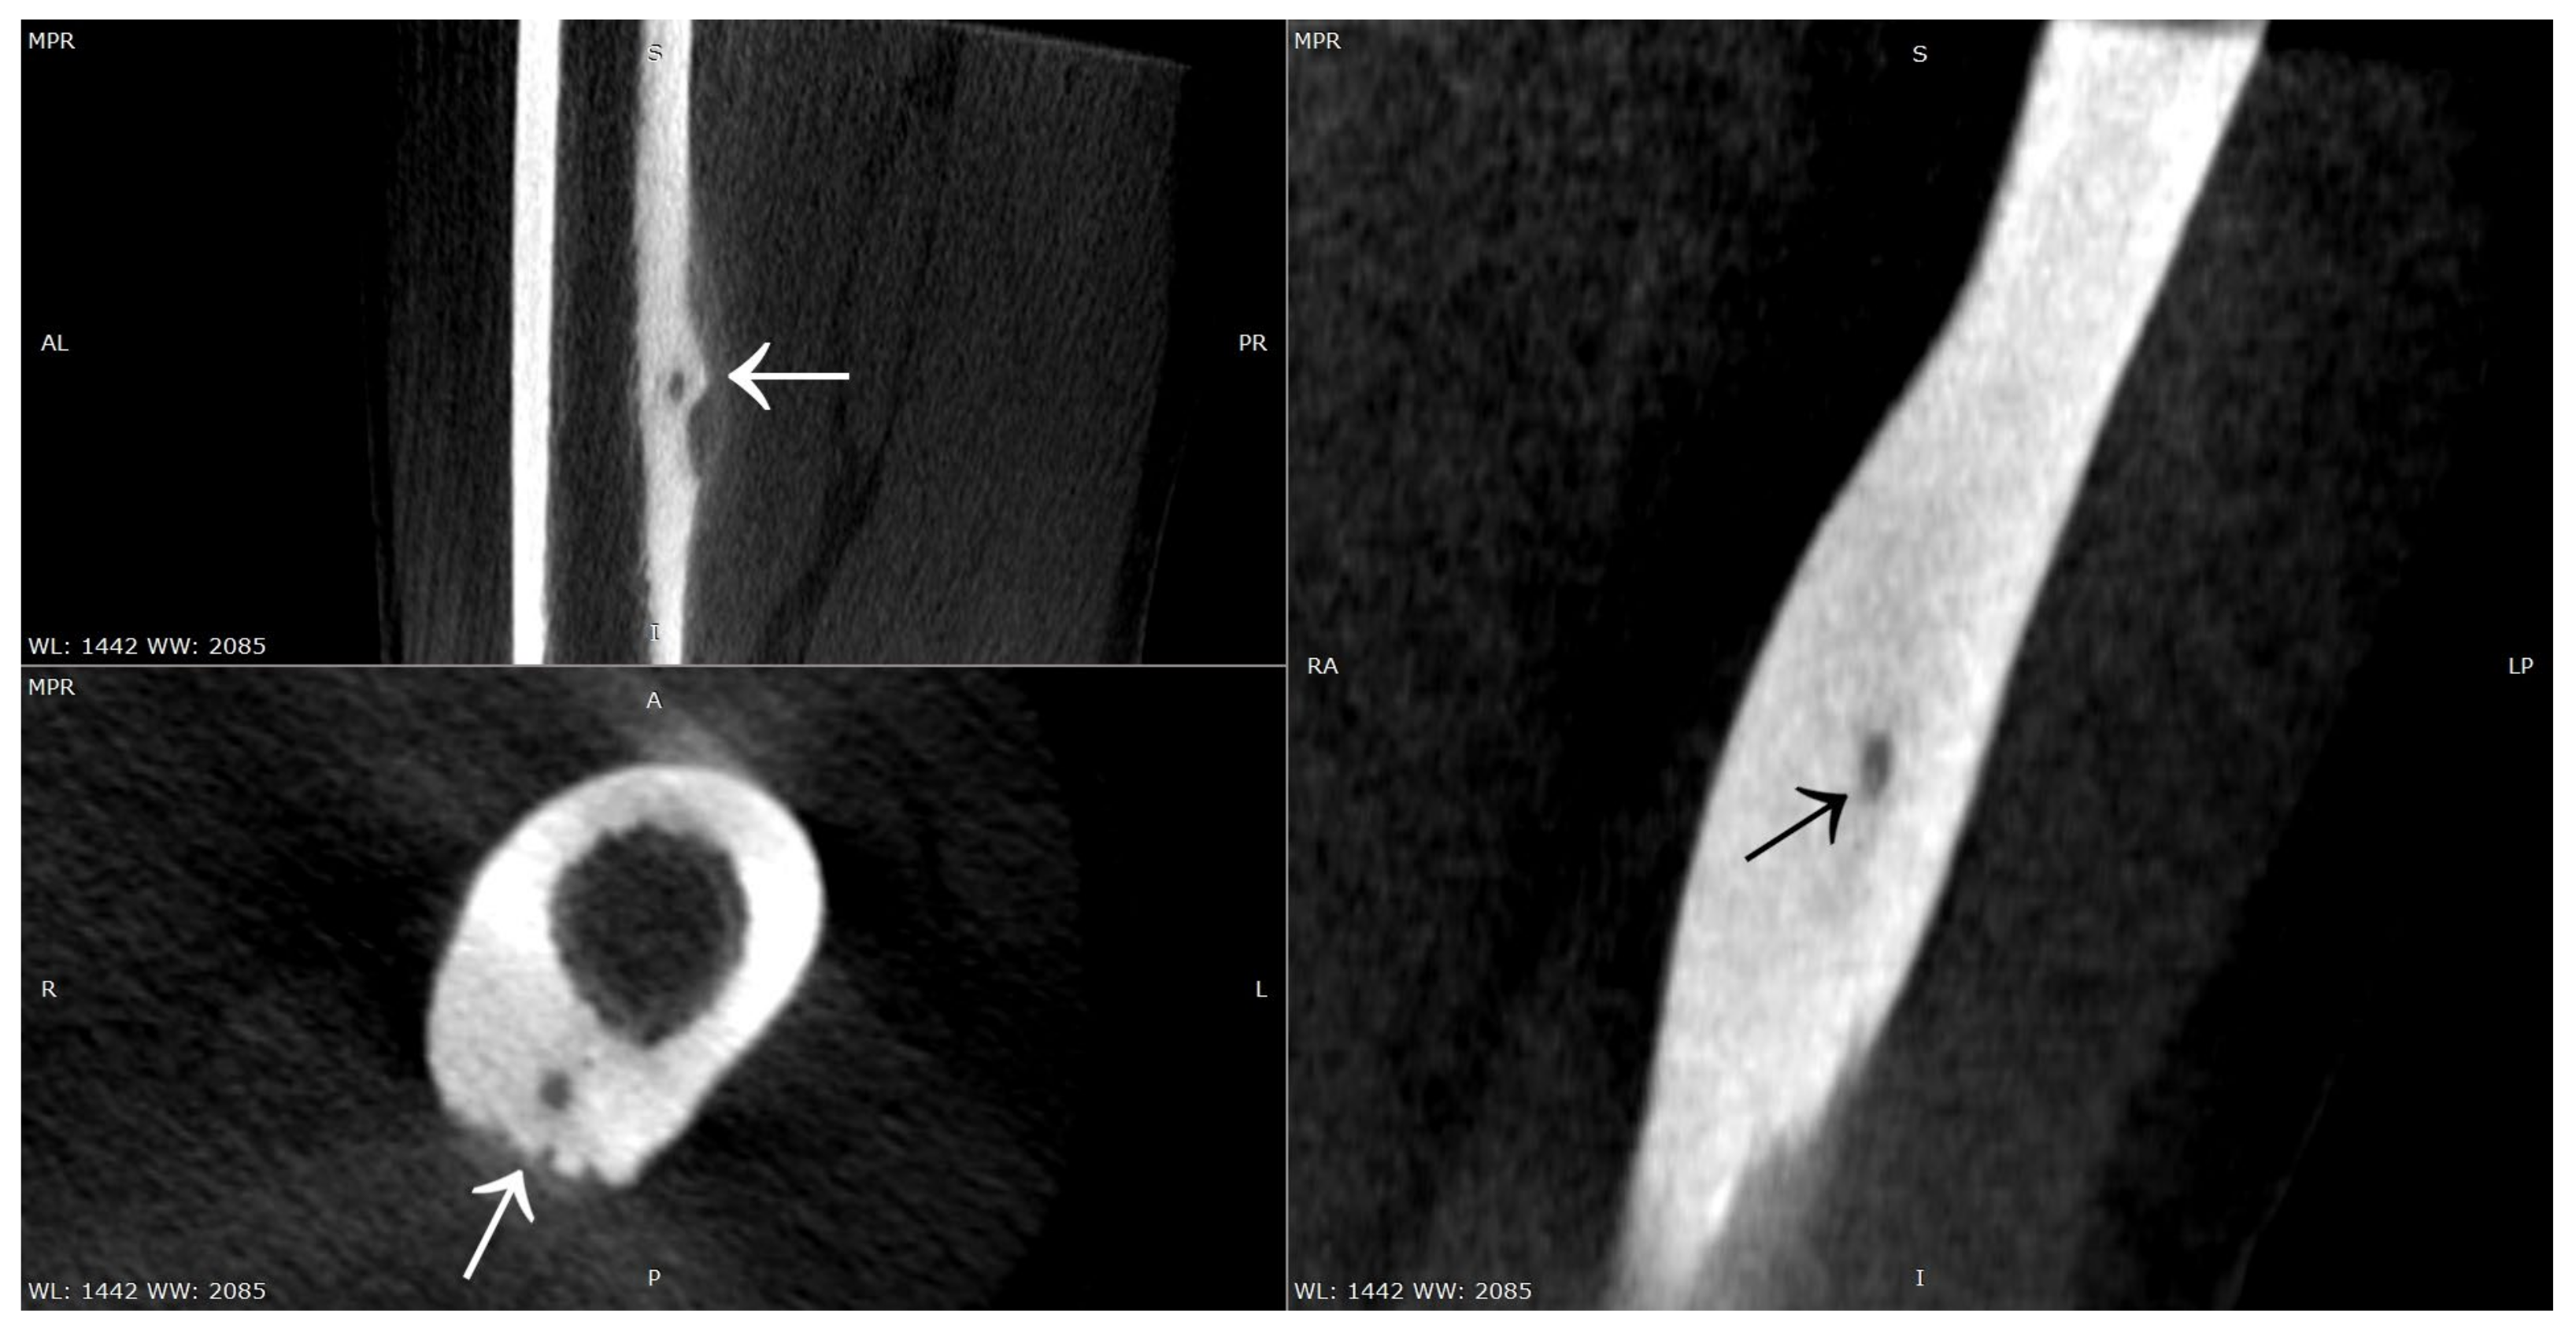

Figure 3.

CT scans of the right femur showing flat cortical bone (arrows) after attempted resection and persistent focus of OO. (a) Frontal CT scan; (b) Transverse CT scan.